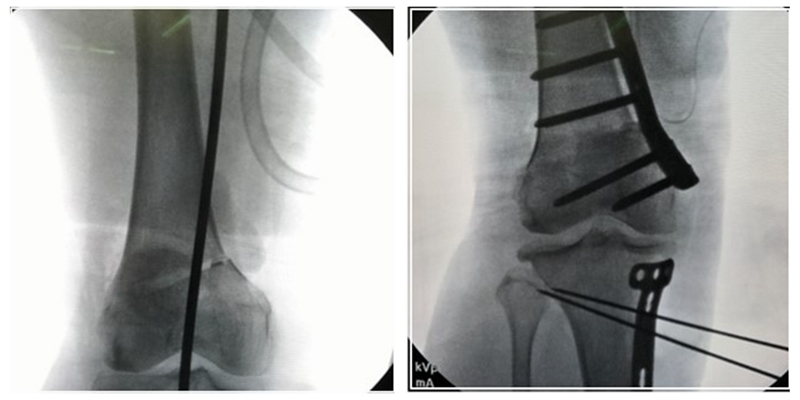

对于手术顺序,提倡先做股骨。当股骨闭合,胫骨开放时,推荐优先做股骨,有利于准确调整下肢力线;当股骨闭合,胫骨闭合,同样推荐先做股骨,不容易发生相应的并发症。但是当出现术前全长片不标准,术前计划不准确时,建议先胫骨,胫骨较容易看关节线。

3、手术的关键

第一侧截骨要把关节线放平;第二侧截骨要达到整体目标力线。

经典病例